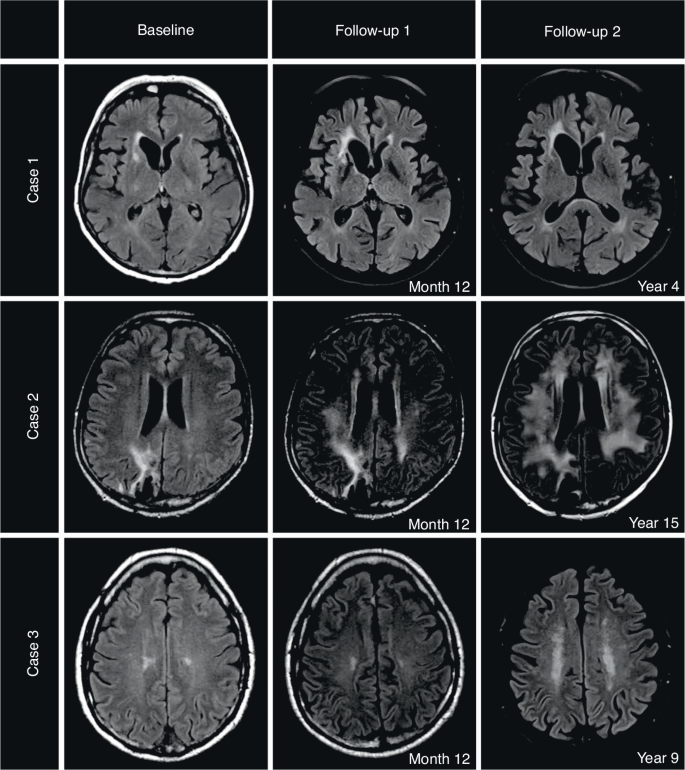

We present three patients with exemplary time courses in Fig. 3.

Case 1: Normal brain aging in a female PCNSL patient, 63 years at diagnosis with a 4-year follow-up period. Low WML burden at baseline (score 0) and at latest follow-up (score 1). Neurocognitive status at year 4: ECOG 0, MMSE 30 points, GHS unknown, QoL subscales all >80%. Case 2: Early WML changes in a male PCNSL patient, 43 years at diagnosis with a 15-year follow-up period. Low WML burden at baseline (score 0) with early conversion to high WML burden at month 12 (score 2). The high WML burden persisted until year 15 (score 3 from month 36 onwards). Neurocognitive status at year 15: ECOG 0, MMSE 28 points, GHS 50%. Case 3: Late WML changes in a male PCNSL patient, 60 years at diagnosis with a 9-year follow-up period. Low WML burden at baseline (score 1) with late conversion to high WML burden at month 60 (score 2). The high WML burden persisted unchanged until year 9 (score 2). Neurocognitive status at year 9: ECOG 0, MMSE 28 points, GHS 91.67.